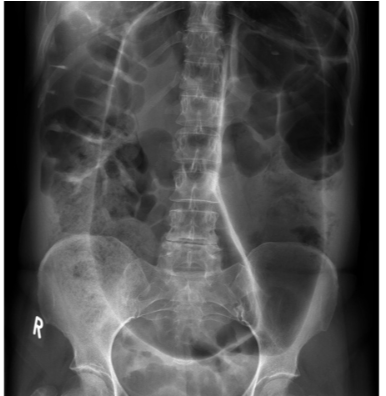

This abdominal X-ray demonstrates multiple dilated loops of bowel with clear valvulae connivente markings. The large bowel is collapsed. **This indicated small bowel obstruction.**